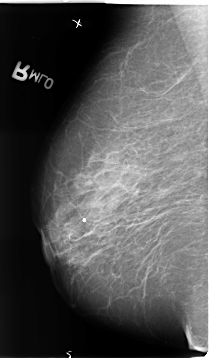

B_3137_1.LEFT_MLO

LEFT_MLO LINES 4688 PIXELS_PER_LINE 2656 BITS_PER_PIXEL 12 RESOLUTION 50 OVERLAY